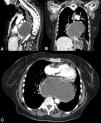

Una mujer de 70 años con antecedente de carcinoma neuroendocrino de células grandes y pequeñas con componente focal de adenocarcinoma de endometrio metastásico a pulmón y antecedente de hernia hiatal grande (>5cm) (fig. 1), ingresó a urgencias por un dolor torácico opresivo, irradiado a cuello y exacerbo con la ingesta de alimentos. Los laboratorios a su ingreso reportaron leucocitos 21.3 ×109/L, neutrófilos 18.3 ×109/L, proteína C reactiva 37.8mg/dL, deshidrogenasa láctica (DHL) 241 UI/L y lactato 2.7 mmol/L; la evaluación de cardiaca sin alteraciones y angiotomografía negativa para tromboembolia pulmonar, sin embargo, se evidenció una hernia hiatal en posición de espejo (fig. 2). Se descomprimió con sonda nasogástrica y ante la sospecha de estrangulación gástrica fue sometida a reducción de hernia hiatal y gastropexia laparoscópica, con mejoría sintomática del dolor. Las hernias del hiato se dividen en cuatro tipos, siendo las más complejas las paraesofágicas (tipo III y IV) que representan el 5-10% (fig. 3). Este tipo de hernias pueden llegar a contener además del estómago, otras vísceras abdominales como el colon, el intestino delgado, el páncreas o el bazo. Las complicaciones agudas como estrangulación o isquemia ameritan descompresión inmediata.

Tomografía computarizada multidetector con contraste intravenoso y reconstrucción multiplanar. Se identifica la presencia del fondo y cuerpo del estómago a nivel intratorácico secundario a hernia para esofágica con importante distensión de la cámara gástrica y del esófago (A) reconstrucción sagital; B) reconstrucción coronal; C) corte axial).